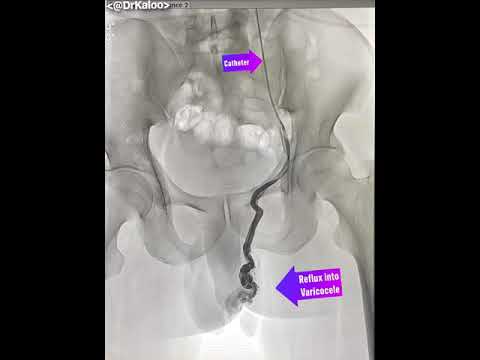

Varicocele Embolisation Angiography (venogram) of left gonadal vein in a man suffering from